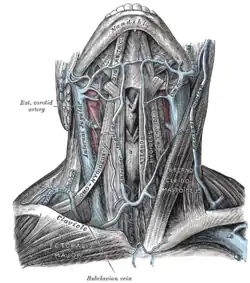

Arterien

Durch den Hals ziehen mehrere große Blutgefäße, die teilweise an der Versorgung des Halses beteiligt sind, teilweise aber ohne Versorgungsfunktion zum Gehirn ziehen. Die beiden Gefäße des Halses, aus denen alle weiteren Gefäße abgehen, sind die Arteria carotis communis und die Arteria subclavia. Rechts entspringen diese beiden Arterien aus dem Truncus brachiocephalicus, links direkt aus der Aorta. Die Arteria subclavia zieht nicht zum Hals, gibt aber die Arteria vertebralis ab, die durch Löcher in den Dornfortsätzen der Halswirbel (Foramina transversaria) hinauf zum Schädel zieht. Daneben gibt sie noch den Truncus thyrocervicalis ab, der sich in eine Reihe von Arterien aufteilt, die im Wesentlichen seitliche Strukturen an der Halsbasis versorgen.[10]

Die Arteria carotis communis verzweigt sich in ihrem weiteren Verlauf in die Arteria carotis interna und die Arteria carotis externa, von denen die Arteria carotis interna keine versorgende Funktion für den Hals einnimmt, sondern zum Gehirn zieht. Im Regelfall (50 Prozent) gehen dann aus der Arteria carotis externa die Arteria thyroidea superior, die Arteria lingualis und die Arteria facialis oberhalb der Bifurkation einzeln ab. Von diesen verzweigt sich die Arteria thyriodea superior in weitere Arterien, die den Kehlkopf, die Schilddrüse und den Musculus sternocleidomastoideus versorgen. Außerdem anastomosiert ein Ast der Arteria thyroidea superior – der Ramus infrahyoideus – mit dem Ast der Gegenseite, so dass eine Verbindung der beiden Arterien hergestellt ist. Die Arteria lingualis versorgt hauptsächlich die Zunge und den Mundboden, über ihre Rami dorsales linguae aber auch den Zungengrund und den Kehldeckel.[11][12]

Weitere Arterien aus der Arteria carotis externa sind die Arteria pharyngea ascendens, die Arteria auricularis posterior, die Arteria occipitalis, die Arteria maxillaris und die Arteria temporalis superficialis, von denen nur die Arteria pharyngea ascendens über ihre Rami pharyngeales einen Teil des Halses versorgt, nämlich Teile des Kehlkopfs.[13]

Venen

Die Venen des Halses sind größtenteils „Durchgangsstraßen“, die das Blut aus dem Kopf zurück zum Herzen führen. Sie verfügen über keine Klappen, sind – da sie oberhalb des Herzens liegen – nur wenig gefüllt und sind normalerweise im Stehen nicht sichtbar. Erst im Liegen beim Gesunden und bei Patienten mit Rechtsherzinsuffizienz auch im Stehen kann man sie erkennen. Die Abflüsse beider Seiten des Halses sind über den Arcus venosus jugularis verbunden. Auf ihn muss bei Tracheotomien wegen der Gefahr von Blutungen geachtet werden. Außerdem sind die Venen untereinander stark anastomosiert, so dass es selbst bei Unterbinden einer größeren Vene nicht zu Blutstauungen kommt.[14]

Die größte Vene des Halses ist die Vena jugularis interna. Sie tritt durch das Foramen jugulare aus der Schädelhöhle heraus und drainiert so das Blut aus dem Gehirn über die venösen Abflüsse der harten Hirnhäute – die Sinus durae matris – und über die Vena facialis, die Vena lingualis, die Vena thyroidea superior und die Venae thyroideae mediae auch Blut aus dem Gesicht und der Schilddrüse.[14]

Die Vena jugularis externa drainiert Blut aus dem oberflächlichen Bereich hinter dem Ohr. Sie verläuft zunächst über der Faszie (Lamina superficialis), aber unter dem Platysma, durchbricht diese dann, um in die Vena subclavia zu münden.[14]

Die Vena jugularis anterior ist variabel ausgebildet und beginnt, wenn sie ausgeprägt ist, unter dem Zungenbein. Sie verläuft nach unten, drainiert Blut aus der vorderen, oberflächlichen Halsregion und mündet zumeist in die Vena jugularis externa.[14]

Die Vena subclavia verbindet sich schließlich mit der Vena jugularis interna zur Vena brachiocephalica, in die außerdem der Plexus thyroideus impar und die Vena vertebralis mündet. Ebenfalls kann die Vena thyroidea inferior hineinmünden. Der Plexus thyroideus impar ist ein venöses Geflecht, das Blut aus der Schilddrüse drainiert. Aus der Verbindung der linken Vena subclavia und Vena jugularis interna entsteht der linke Venenwinkel, in den der Ductus thoracicus einmündet. Die Vena subclavia rechts und links verbinden sich schließlich zur oberen Hohlvene, die das Blut zum Herzen befördert.[14]